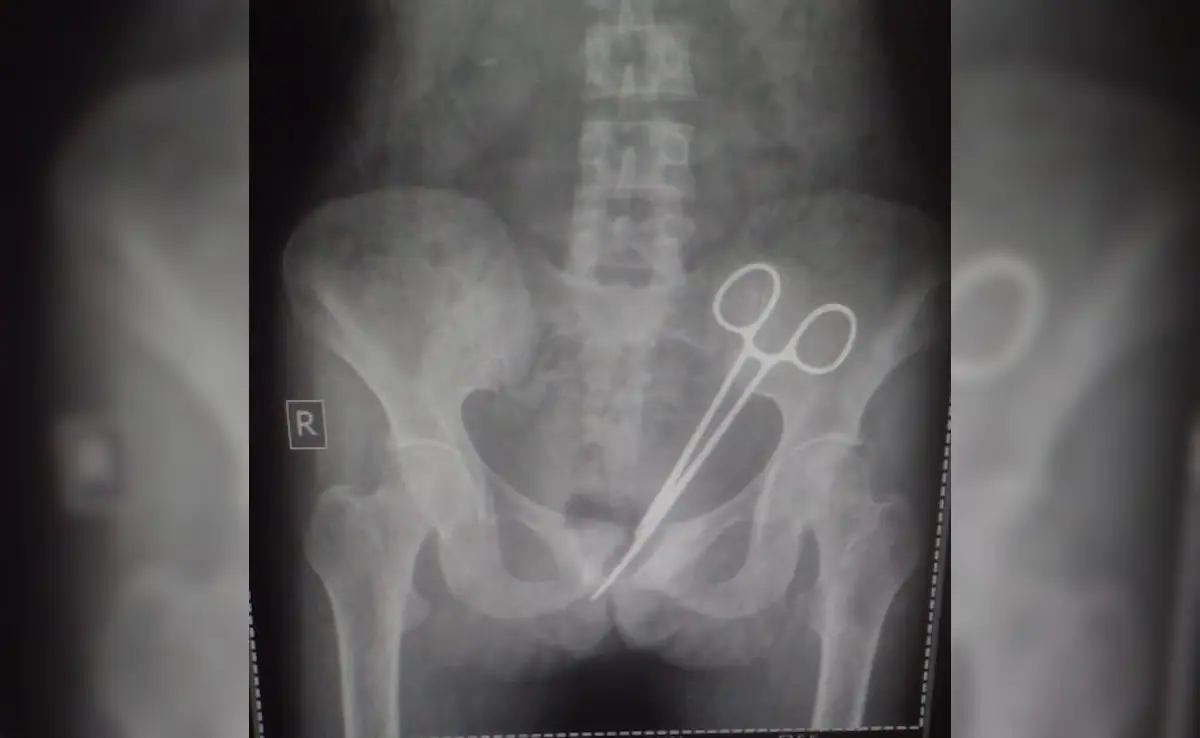

Kerala medical case : केरल से चिकित्सा लापरवाही का एक चौंकाने वाला मामला सामने आया है, जिसमें एक महिला को ऑपरेशन के बाद पाँच वर्षों तक असहनीय दर्द झेलना पड़ा। सर्जरी के दौरान पेट में छूटा एक सर्जिकल उपकरण पहचाने बिना टांके लगा दिए गए, जिसके कारण वह लंबे समय तक बीमार रहती रही।

अलप्पुझा की रहने वाली उषा जोसेफ ने 2021 में गर्भाशय संबंधी समस्या के इलाज के लिए सरकारी मेडिकल कॉलेज अस्पताल में सर्जरी कराई थी। आरोप है कि ऑपरेशन के दौरान डॉक्टरों ने गलती से सर्जिकल फोर्सेप्स उनके पेट के अंदर ही छोड़ दिए। सर्जरी के बाद उन्हें लगातार पेट दर्द होता रहा, लेकिन कई बार अस्पताल जाने के बावजूद उनकी शिकायत को गंभीरता से नहीं लिया गया।

आखिरकार दर्द असहनीय होने पर उन्होंने एक निजी अस्पताल का रुख किया, जहां एक्स-रे जांच में पेट के अंदर धातु का उपकरण दिखाई दिया। यह देखकर परिवार और मरीज दोनों स्तब्ध रह गए और मामला चिकित्सा लापरवाही का गंभीर उदाहरण बन गया।